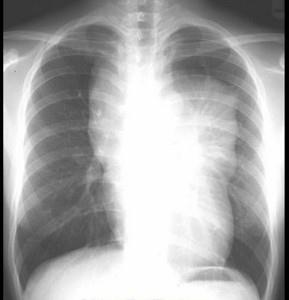

问题 18岁,男,咳嗽头晕一个月,请结合胸片和CT检查,选出最可能的诊断 ( )

选项 A、胸内甲状腺瘤 B、神经源性肿瘤 C、淋巴瘤 D、畸胎瘤 E、胸腺瘤

答案 D